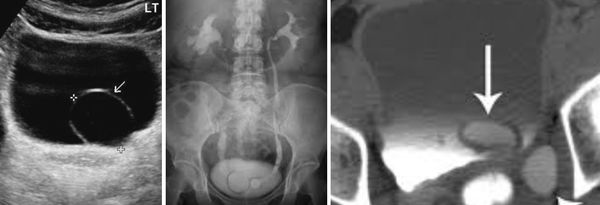

Болюсное введение контрастного вещества и последующее динамическое исследование различных фаз контрастирования способствует четкому выявлению уретероцеле (рис. 3б).

Уретероцеле обнаружено у 3 (8,1%) пациентов из 37. Этот порок уретеровезикального сегмента на МСКТ характеризовался с кистовидным расширением внутрипузырного сегмента мочеточника. При этом отчетливо определяется округлая полость, вдающаяся в просвет мочевого пузыря (рис. 3).

Рис 3. МСКТ картина уретероцеле. Трехмерная реконструкция. Удвоение почек и мочеточника справа (a) и уретероцеле слева (б)